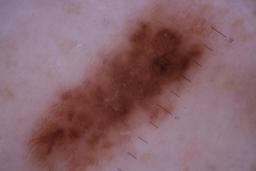

ISIC_6742970

- Sydney Melanoma Diagnostic Center at Royal Prince Alfred Hospital, Pascale Guitera

- Challenge 2020: Training

Clinical

| Field | Value |

|---|---|

| acquisition_day | 91 |

| age_approx | 75 |

| anatom_site_1 | Trunk |

| anatom_site_2 | Posterior trunk |

| concomitant_biopsy | False |

| diagnosis_1 | Benign |

| diagnosis_confirm_type | serial imaging showing no change |

| fitzpatrick_skin_type | I |

| image_type | dermoscopic |

| lesion_id | IL_7403129 |

| patient_id | IP_4261345 |

| sex | male |